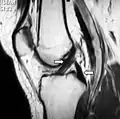

رباط صَلیبی پسین (صلیبی خلفی، متقاطع پشتی یا PCL) (به انگلیسی: Posterior cruciate ligament) یکی از رباطهای قوی مفصل زانو است. این رباط از کوندیل داخلی فمور (استخوان ران) به ناحیه پشتی بین کوندیلی تیبیا (درشت نی) متصل میگردد.[1] رباط متقاطع پشتی (PCL) و متقاطع جلویی (ACL) داخل کپسولی بوده [2] و به علت وضعیت آناتومیکی خاص به نام متقاطع یا صلیبی نامیده میشوند.

اگر کپسول مفصلی زانو از عقب باز گردد، اولین قسمتی که مشاهده میگردد، رباط متقاطع پشتی است.[3] این رباط نسبت به رباط متقاطع جلویی، قوی تر بوده، ولی فیبرهای رباط متقاطع جلویی، وضعیت مایل تری دارند.[1] مهمترین عمل رباط متقاطع پشتی، جلوگیری از دررفتگی تیبیا (درشت نی) به سمت عقب است.

خم شدن یا صاف شدن بیش از اندازه مفصل زانو (هیپرفلکسیون یا هیپراکستانسیون) ممکن است باعث آسیب این رباط (PCL) گردد.[4] همچنین ضربه شدید به انتهای فوقانی درشتنی همراه با خم بودن زانو، میتواند پارگی رباط صلیبی پسین را به دنبال داشته باشد.[5] آسیب این رباط منجربه افزایش جابجایی درشتنی به سمت عقب میگردد.[4] پارگی PCL به صورت مجزا کمتر اتفاق میافتد و معمولاً با پارگی رباطهای دیگر زانو و منیسکها همراه است.[4][5]